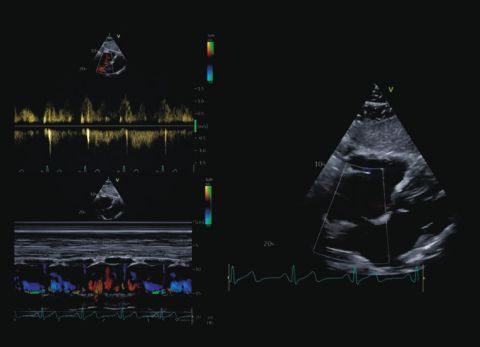

Wideo Echokardiografia. Przypadek 9

prof. dr hab. n. med. Zbigniew GąsiorPacjent z trzepotaniem przedsionków; w wywiadzie niewielkie pogorszenie tolerancji wysiłku i napadowe kołatania serca od około roku.